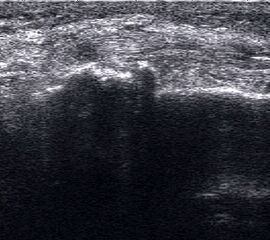

Ruptur Lig. fibulocalcaneare

Längsschnitt über dem Lig. fibulocalcaneare. Die Peronealsehnen erscheinen als echoreiche runde bis ovaläre Struktur.

Abbildung 19

Lagerung: Rückenlage, OSG in Neutralstellung.

Schnittebene: LS über Lig. fibulocalcaneare.

Referenzstrukturen: Fibulaspitze und Talus.

Befunde: Das Lig. fibulocalcaneare is nativ schlecht abgrenzbar, da es in die Tiefe und nicht parallel zum Schallkopf verläuft. Direkt über das Band ziehen quer getroffen die Peronäussehnen. Durch die Distorsion kann auch das Peritendineum peroneale einreißen. Die Peronealsehnen sind dann in ihrer Sehnenscheide von Blut umgeben, was sich als echoarmer Ring (Halo-Phänomen) darstellt und ein indirektes Zeichen für eine Verletzung des Lig. fibulocalcaneare ist.